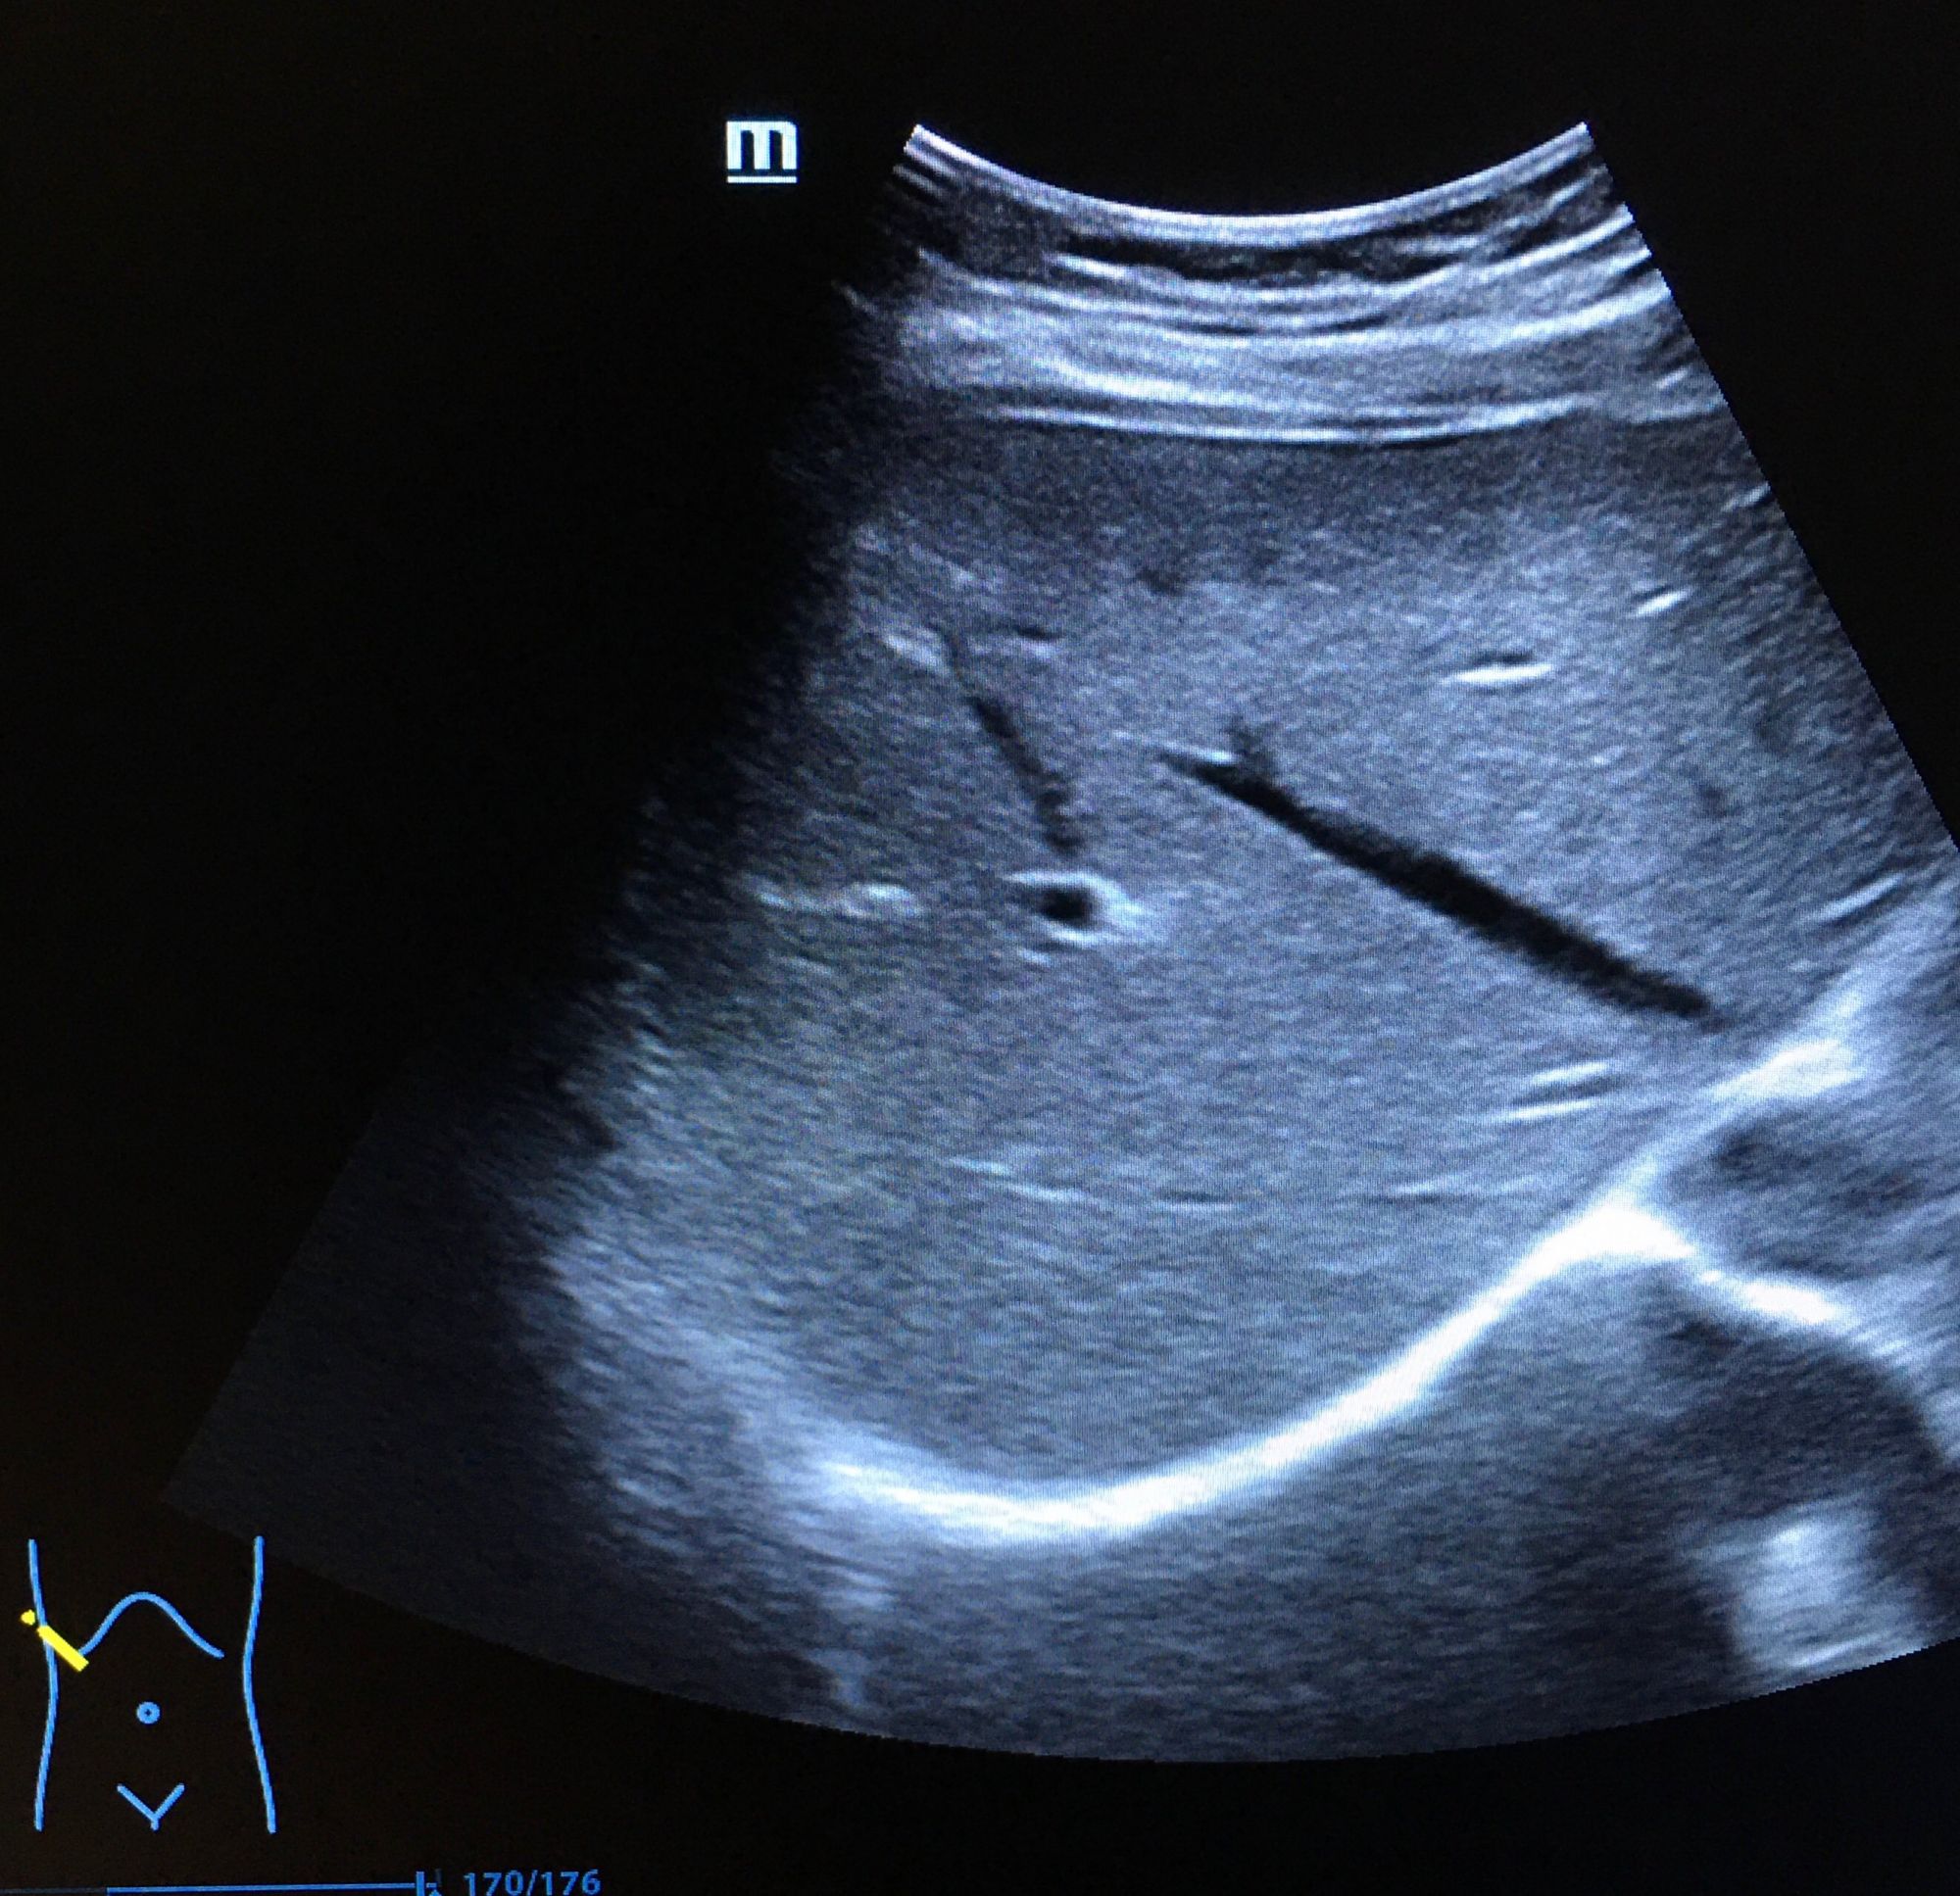

二、超聲成像

是一種基于超聲波的成像技術(shù)。超聲波在生物體內(nèi)傳播時,遇到不同的組織會產(chǎn)生不同的回聲信號,通過分析這些信號可以獲取生物體的內(nèi)部結(jié)構(gòu)和功能信息。超聲成像具有無創(chuàng)、無痛、無輻射等優(yōu)點,因此在臨床診斷和生命科學(xué)研究中得到了廣泛應(yīng)用。

超聲成像